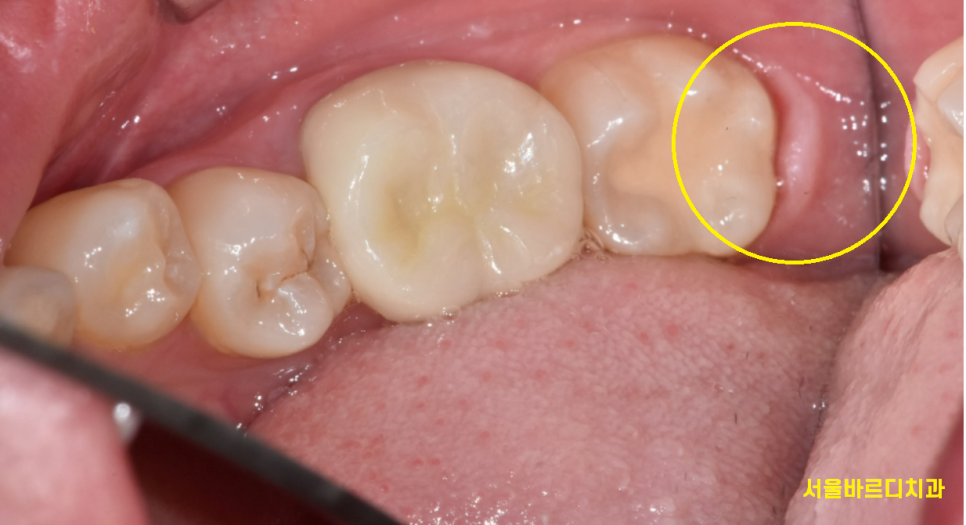

240731

앞에 치아까지 충치가 먹어버렸네요..

아무리 예쁘게 올라온 사랑니도

관리가 안되면 이렇게 됩니다.